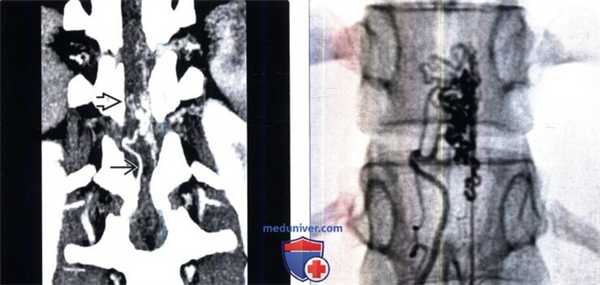

(Слева) Сагиттальный срез, STIR МР-И: гиперинтенсивность сигнала на всем протяжении спинного мозга и нечетко ограниченные сосудистые полости вдоль вентральной его поверхности. Также виден ограниченный участок низкого сигнала, который при проведении ангиографии оказался высокопоточной аневризмой.

(Справа) На ангиограмме в прямой проекции (артериальная фаза) контрастирован крупный сегментарный питающий сосуд спинного мозга, кровь из которого напрямую, без промежуточного узла, шунтируется во фронтальное венозное сплетение. В области фистулы образовалась высокопоточная аневризма.